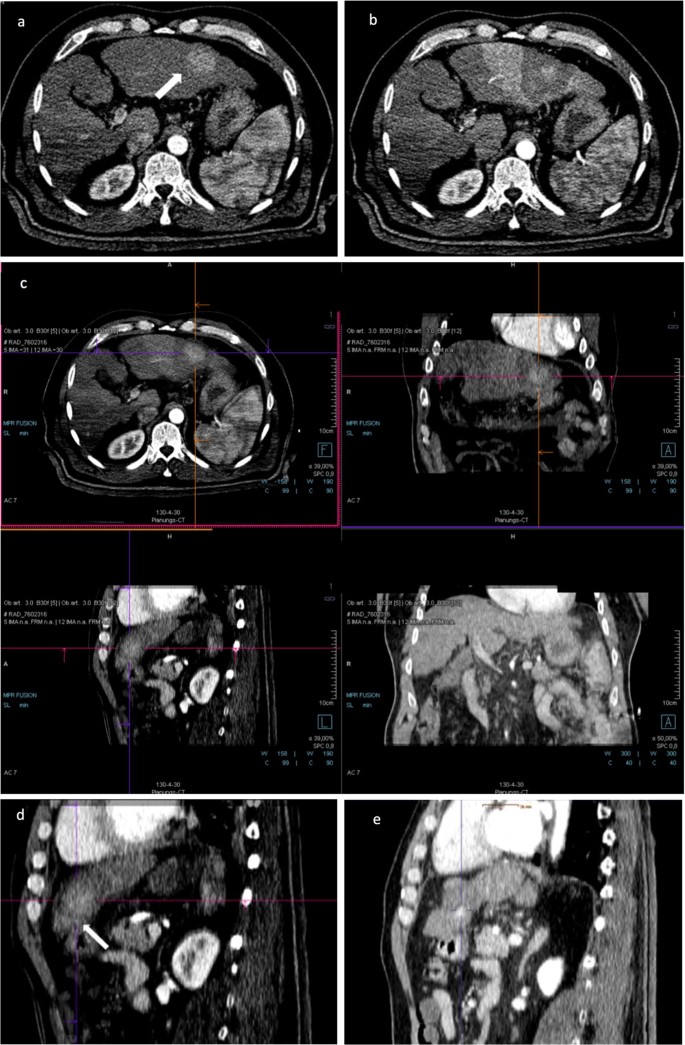

Fig. 3

figure 3

A 63-year-old male patient treated with stereotactic RFA. a The arterial phase of pre-SRFA CT scan depicting a single HCC lesion (arrow) with a maximal diameter of 3.4 cm in liver segment II. b The arterial phase of post-SRFA CT scan with transient hyperemic rim around the ablation zone. c The after fusion of pre- and post-SRFA CT scan with manual registration by slight shifting (translation and rotation) in axial, coronal, and sagittal planes referring to intrahepatic structures such as vessel bifurcations. d The sagittal plane of CT image fusion with a MAM of 2.2 mm in clock position 5–6 h (arrow). e Local tumor progression after stereotactic RFA: contrast-enhanced CT scan 20.2 months after stereotactic RFA revealing a hypervascular, contrast-enhancing lesion in the arterial phase and with washout in delayed phase that is located immediately adjacent to the ablation zone